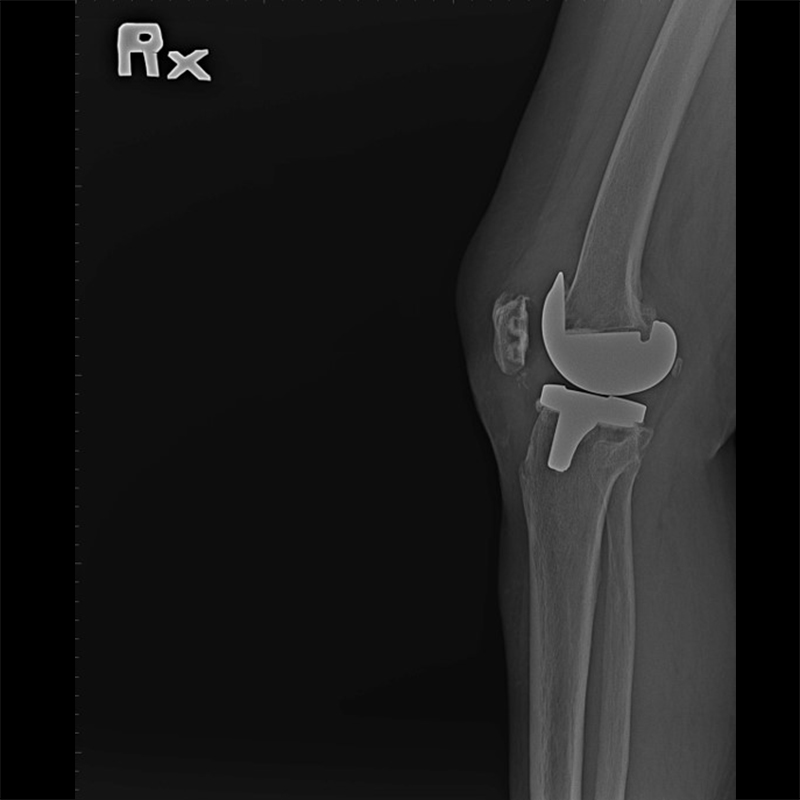

外院失敗本院再置換 首頁 案例分享 膝關節手術 外院失敗本院再置換 蕭女士 69歲 術前 術後 81歲 林女士 術前 術後 蕭女士 69歲 術前 術後 鄒女士 69歲 術前 術後 李女士 74歲 術前 術後 吳女士 71歲 術前 術後 謝女士 65歲 術前 術後